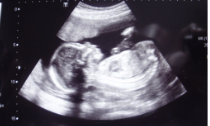

복부초음파 /검사주기 /검사비용 /복부초음파 주의사항 알아보아요. 복부초음파 검사는 고주파 음파를 이용하여 복부 내부 영상을 생성하는 검사입니다. 복부 내장기관과 혈관의 상태를 파악하여 종양, 낭종, 결석, 염증 등을 진단할 수 있습니다. 또한, 췌장염, 담낭염 등 복부 내 염증 질환, 복부 내출혈의 유무, 복부 기형, 소화기관의 상태 등을 파악할 수 있습니다. 검사는 대부분 건강보험 적용 대상이며 안전한 검사 방법입니다. 검사 결과는 전문의가 진단 및 해석을 하게 되며, 추가 검사나 치료가 필요한 경우에는 전문의의 조언을 따라야 합니다.

복부초음파는 복부 내부 구조물을 검사하여, 다양한 복부 질환의 진단과 치료 등에 활용되는 검사 방법입니다. 이러한 검사를 통해 복부 내부의 각종 기관과 조직들의 상태를 파악할 수 있습니다.

복부초음파 검사는 다양한 이유로 시행됩니다. 대표적인 이유로는 다음과 같습니다.

- 위, 췌장, 담도, 담낭 등 복부 내부에 발생하는 종양, 낭종, 염증, 출혈 등의 질환을 진단하고, 이들의 크기, 위치, 형태, 수치 등을 파악하기 위해 시행됩니다.